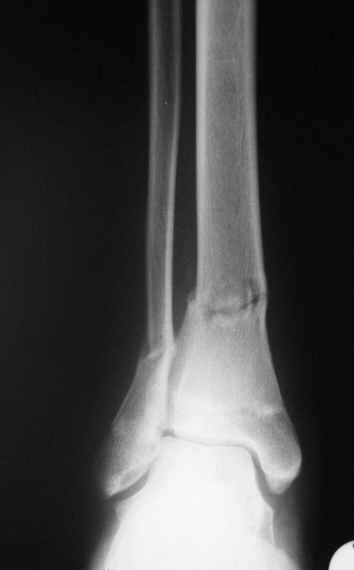

дистальный тиб.фиб. перелом |

Больной 17 лет , 3 недели с момента травмы, был переведен в наше отделение из соседнего

госпиталя.

Попытка закрытой ручной репозиции, предпринятая ранее в этой больнице,оказалась безуспешной, что и явилось причиной перевода к нам.

Чтобы вы предложили в данной ситуации?

Показана ли фиксация перелома малоберцовой кости в данном случае или в этом нет необходимости?